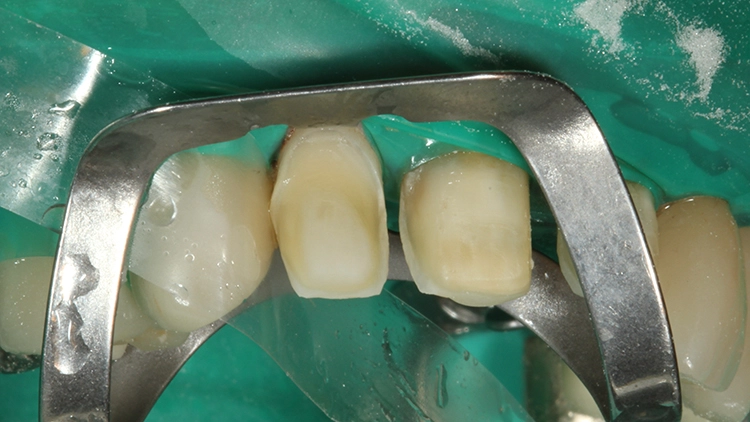

In der Abbildung 15 ist die Teilkrone für den Zahn 11 mit dem fast vollständig evaporierten Primer zu sehen. Zeigt sich ein derartiges Evaporationsbild vorzeitig, muss Material nachappliziert werden. Die Verklebung von Veneers und Teilkronen unter Kofferdammisolierung ist sicherlich sinnvoll.

Ebenso sinnvoll ist es, Teilkronen einzeln zu verkleben und nach Versäuberung des Befestigungskomposits die als nächstes zu verklebende Teilkrone nochmals einzuprobieren. Verständlicherweise erfolgt dann erst die Vorbehandlung dieser Teilkrone. (Auch jetzt kann trotz Kofferdamm immer nochmal eine Klebeflächenkontamination passieren.)

Ein weiterer Polymerisationszyklus wurde unter Glyceringel-Applikation der Klebefuge durchgeführt: Die Polymerisation der Klebefuge unter Sauerstoffabschluss durch das Glyceringel (hier die Try-In-Paste von Visalys CemCore) hindurch erlaubt eine vollständige Aushärtung an der Oberfläche: Somit wird eine Farbstabilität des Befestigungskomposits garantiert und gleichzeitig ein „Auswaschen“ insuffizient ausgehärteten Materials direkt an der Oberfläche der Klebefuge verhindert. Nach der vollständigen Befestigung und Überschussentfernung der Teilkrone auf Zahn 11 wurde die Zahnhals-Kofferdammklammer an Zahn 21 umpositioniert (Abb. 18) und die Teilkrone für den Zahn 21 (Abb. 19) nach Einprobe und Vorbehandlung unter denselben Kautelen wie an Zahn 11 verklebt. Auch die Vorbehandlung der Klebefläche am Zahn (Rondoflex-Abstrahlen, Phosphorsäurekonditionierung, Visalys Tooth Primer-Applikation) erfolgte vorab separat.